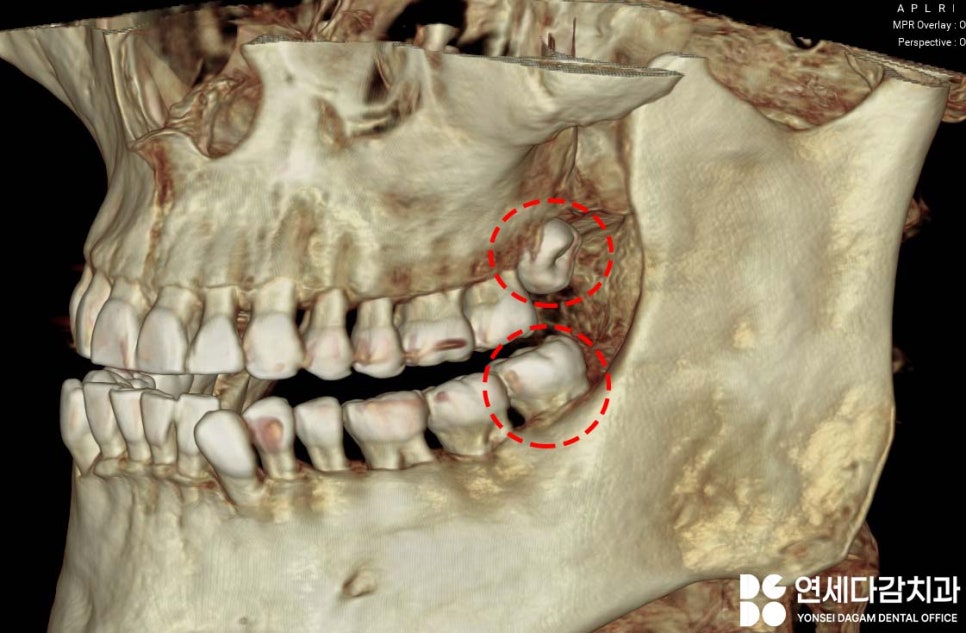

CT로 3차원적인 구조를 분석하면

치아가 어떤 방향으로 나 있는지,

주변 구조물과 얼마나 가까운지,

뿌리의 형태 또한 정밀하게 파악할 수 있는데요.

이렇게 수평으로 누워서

부분적으로 매복된 상태입니다.

수평 매복 사랑니란

치아가 옆으로 누워서

잇몸이나 뼈 속에 묻혀있는 상태를 말합니다.

부분적으로 나와있는 경우도 있는데,

매복된 경우나 부분 맹출 된 경우는

정상적으로 나온 사랑니보다

빼기가 까다롭습니다.

더군다나 해부학적 구조물과

가깝다면 더 유의해야 됩니다.